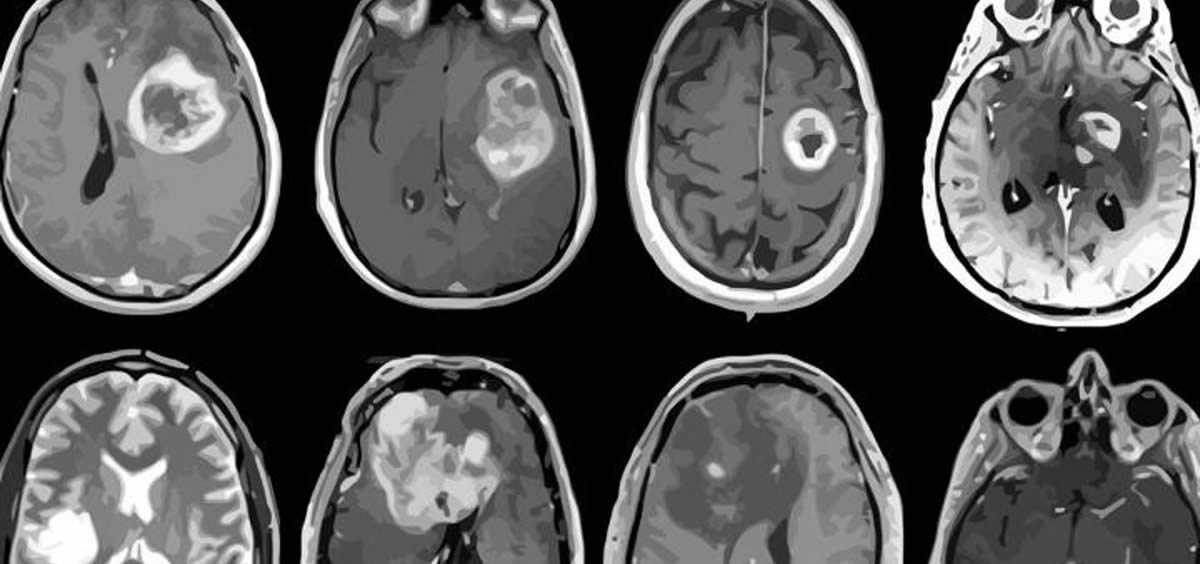

A pesar de los importantes avances descubiertos durante estos años, la mortalidad de los tumores cerebrales sigue siendo elevada, con una tasa de supervivencia a cinco años del 36%, según el Instituto Nacional del Cáncer de Estados Unidos. Las opciones actuales de biopsias de tejido y los métodos basados en la imagen todavía tienen muchas carencias, por ello, cobra una mayor importancia de nuevas técnicas.

Para conseguir tratar eficazmente el cáncer cerebral, los profesionales necesitan confirmar la presencia de un tumor maligno, identificar dónde se originó y si se trasladó desde otros órganos. Ninguna técnica de diagnóstico existente puede lograr saber estos datos sin cirugía o una dolorosa punción lumbar, por esta razón, los investigadores querían desarrollar una prueba no invasiva utilizando una pequeña cantidad de suero.